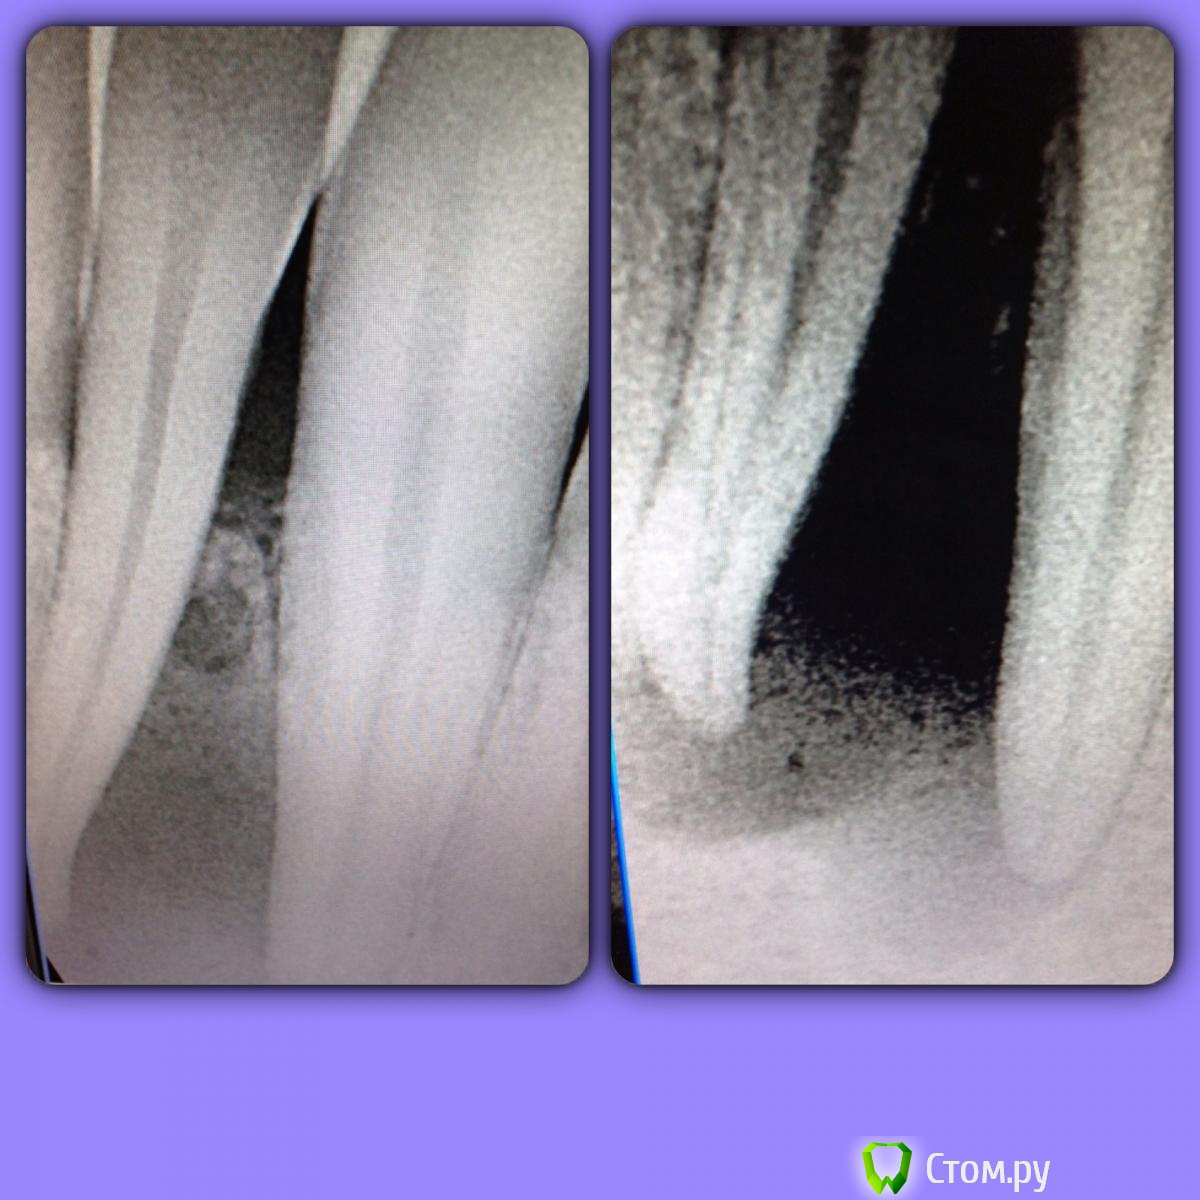

SSTi Опубликовано 10 июня, 2014 Автор Поделиться Опубликовано 10 июня, 2014 32 зуб. На верхушке большое разрежение. Холодовой тест показал, что 31 жив, 32 погиб смертью храбрых, 33 жив. С язычной стороны свищ. В первое посещение открылись, помылись , канал для нижней двойки широкий очень. Обработка до ф2 , упор 40.02. Кальций. Во второй визит- вымываем кальций, пломбируем. Свищ закрылся. Клык пока не трогал. Ссылка на комментарий

SSTi Опубликовано 10 июня, 2014 Автор Поделиться Опубликовано 10 июня, 2014 Кармана нет, снова делал больше контраст. С вестибулярки не так плохо. Язычно тоже. Подвижности нет. Ссылка на комментарий

faity Опубликовано 10 июня, 2014 Поделиться Опубликовано 10 июня, 2014 по отсроченным результатам кость долго восстанавливается? Ссылка на комментарий

SSTi Опубликовано 10 июня, 2014 Автор Поделиться Опубликовано 10 июня, 2014 Здесь думаю от года и больше 1 Ссылка на комментарий